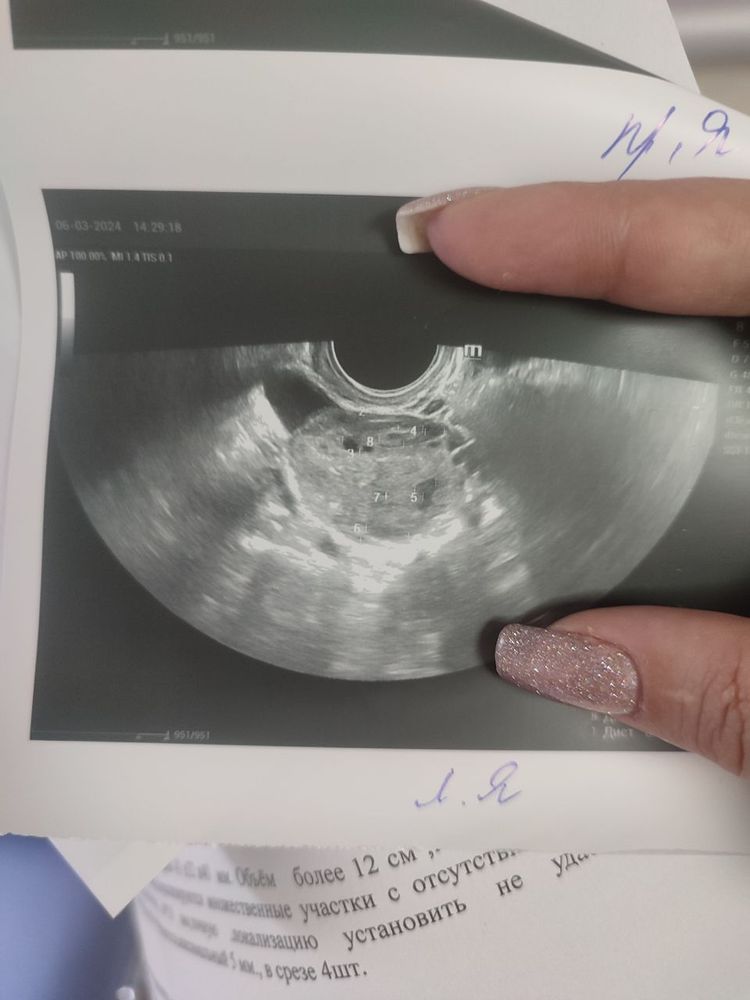

Прошу советаПосле пункции прошло 9 дней, месячных нет,левый яичник болит так,что я готова на стену лезть,сходила сегодня на УЗИ.Может кто подскажет было ли у вас такое?

После пункции прошло 9 дней, месячных нет,левый яичник болит так,что я готова на стену лезть,сходила сегодня на УЗИ.Может кто подскажет было ли у вас такое?